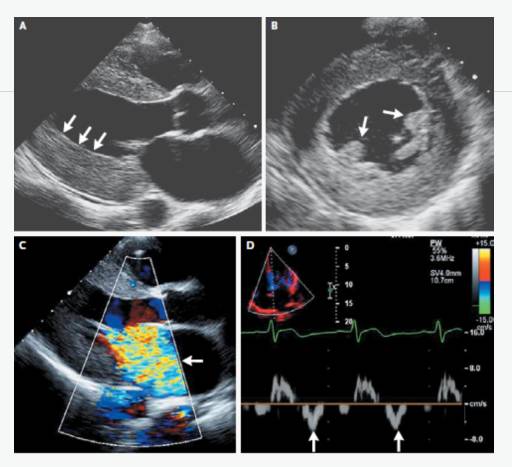

UCG示“先天性主动脉瓣发育不良,主动脉瓣二叶瓣,主动脉瓣狭窄伴轻度关闭不全,主动脉瓣赘生物形成,左心轻大,心功能正常”。

ECHO:瓣膜赘生物。

UCG示“主动脉瓣位生物瓣瓣架表面赘生物形成”,考虑“感染性心内膜炎”。

ECHO:

主动脉瓣生物瓣赘生物;

瓣周漏。

UCG示“重度主动脉瓣瓣周漏,主动脉瓣中重度狭窄,各瓣膜未见赘生物”Coxiella burnetii抗体持续升高,提示感染持续存在。